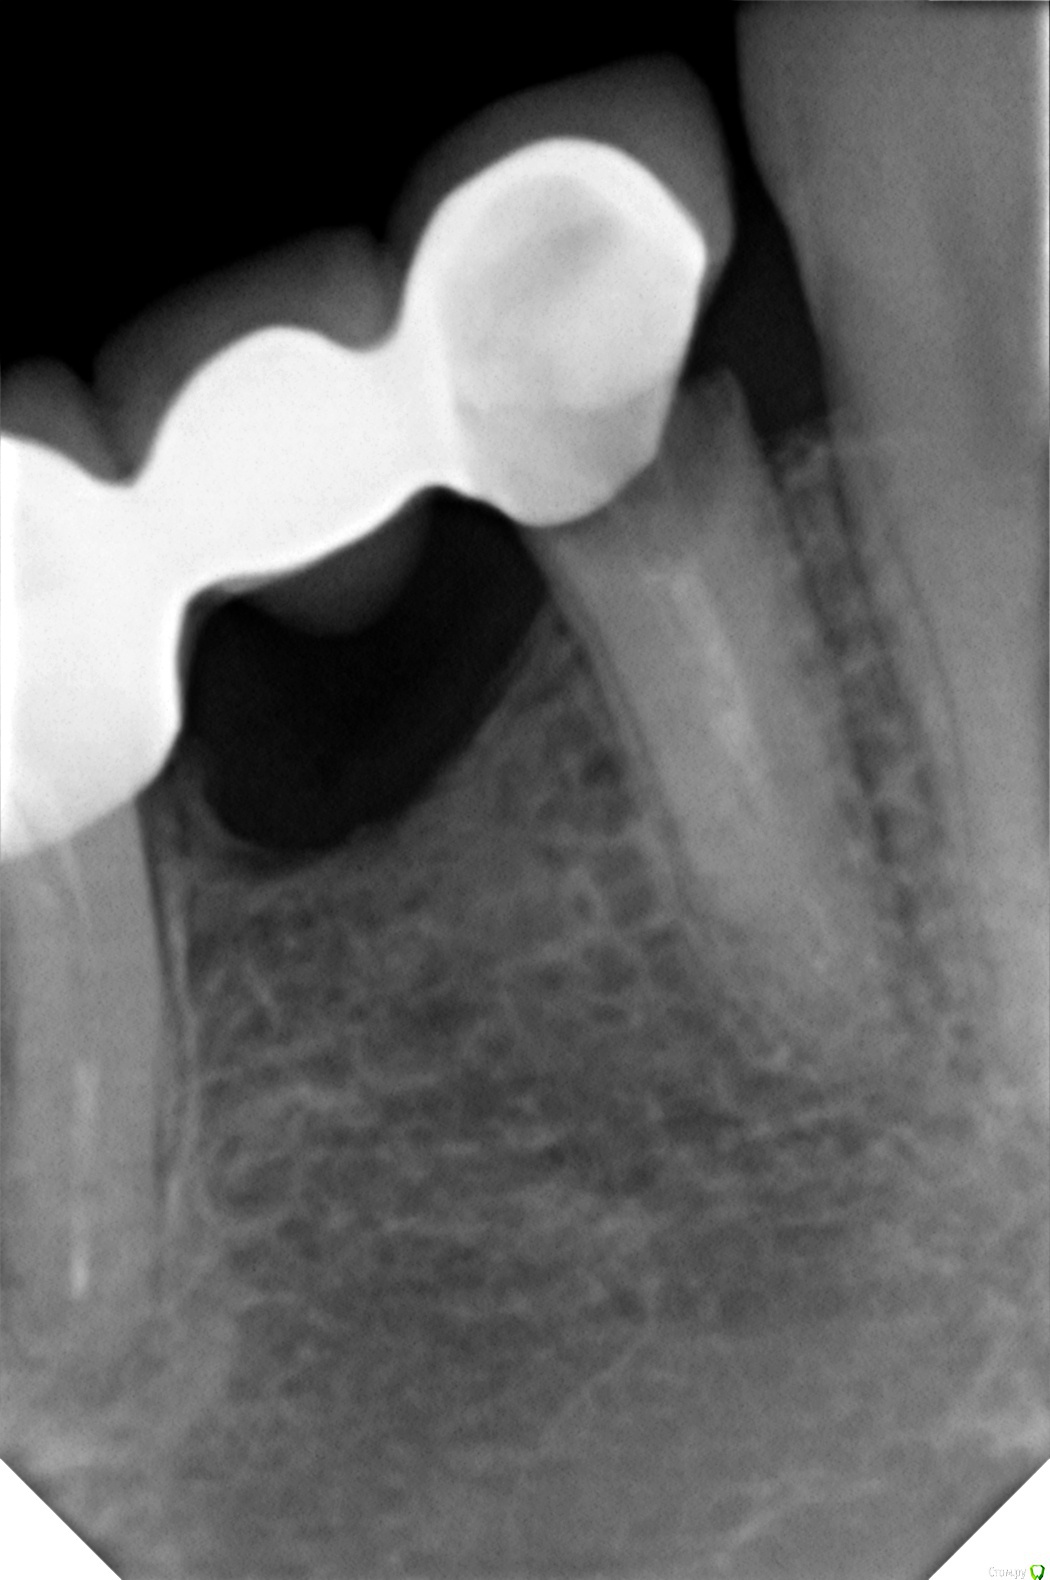

Винкс Опубликовано 25 мая, 2015 Поделиться Опубликовано 25 мая, 2015 Речть идет про правый низ. Сняли мост 4-5-6-7.Приговор: 4 на удаление, потом имплант. 5 - имплант, 7 пролечили.Вопрос стоит про 6. Каналы не удалось распломбировать, там "камень" по словам доктора. Что с ней делать? Оставить так или удалить?Если удалить, то как вы смотрите на мост на двух имплантах.Если это тема не для терапии, то перенесите плз. Дополнительно. Ссылка на комментарий

Гарриевич Опубликовано 25 мая, 2015 Поделиться Опубликовано 25 мая, 2015 если притензии к зубу только по каналам. тоотмыть и запломбировать по проходимости Ссылка на комментарий

Alejandro Опубликовано 29 мая, 2015 Поделиться Опубликовано 29 мая, 2015 (изменено) Нет пока повода для паники. Смело инсталируйте имплантаты в области премоляров, если клиники в первом моляре нет и не было. Больше беспокоит карман между 6 и 7. Шестёрка со временем уйдёт, но как и когда никто не скажет. Уйдёт шестёрка - ещё один имплантат. Изменено 29 мая, 2015 пользователем Alejandro Ссылка на комментарий

Винкс Опубликовано 1 июня, 2015 Автор Поделиться Опубликовано 1 июня, 2015 Нет пока повода для паники. Смело инсталируйте имплантаты в области премоляров, если клиники в первом моляре нет и не было. Больше беспокоит карман между 6 и 7. Шестёрка со временем уйдёт, но как и когда никто не скажет. Уйдёт шестёрка - ещё один имплантат.Вот вы мне написали про карман... После ирригатора отдуда кровит постоянно после снятия моста. Я сначала думала, что там ткани не привыкшие к струе, но уже целый месяц прошел. Ссылка на комментарий